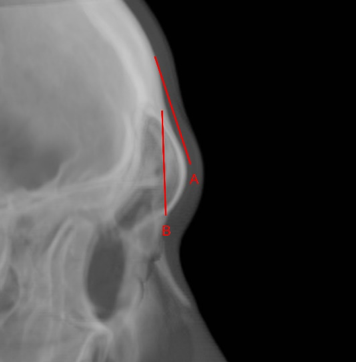

- 前額填充物與前額後推手術比較:

- 前額填充物(A)

額角縮小,沒有影響鼻額角。 - 前額後推手術(B)

額角縮小,鼻額角放大,較能達到額頭柔化手術要求